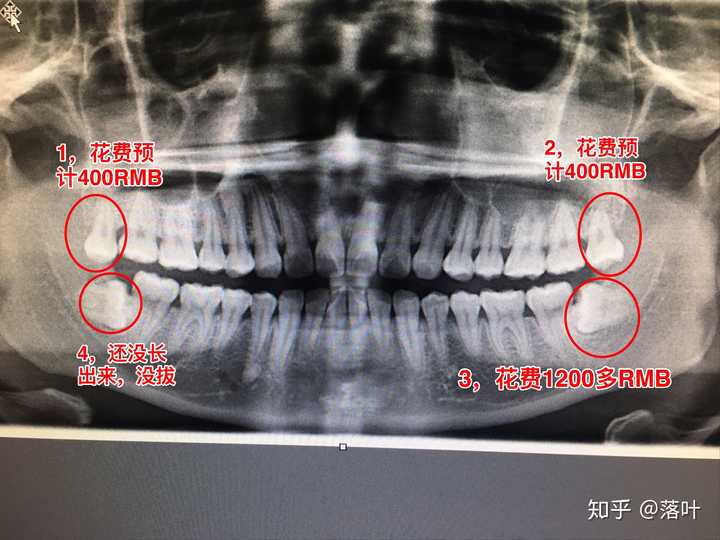

智齿牙片,小牙片图片

(圆圈所示为智齿,箭头所示为多生齿)

1,先介绍一下我牙齿的情况 请看牙片,上面2颗是都长出来的智齿,上面

分享一下我的牙片 以及上面的智齿需要拔吗

智齿发炎拍了牙片…感觉人生从此转折_(:з」∠)